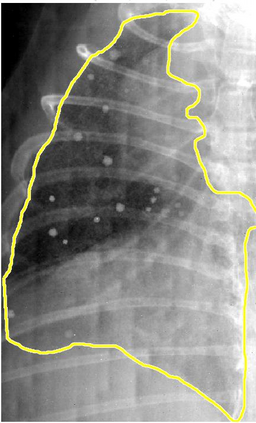

Low-dose computed tomography (LDCT) is the current standard for lung cancer screening, yet its adoption and accessibility remain limited. Many regions lack LDCT infrastructure, and even among those screened, early-stage cancer detection often yield false positives, as shown in the National Lung Screening Trial (NLST) with a sensitivity of 93.8 percent and a false-positive rate of 26.6 percent. We aim to investigate whether X-ray dark-field imaging (DFI) radiograph, a technique sensitive to small-angle scatter from alveolar microstructure and less susceptible to organ shadowing, can significantly improve early-stage lung tumor detection when coupled with deep-learning segmentation. Using paired attenuation (ATTN) and DFI radiograph images of euthanized mouse lungs, we generated realistic synthetic tumors with irregular boundaries and intensity profiles consistent with physical lung contrast. A U-Net segmentation network was trained on small patches using either ATTN, DFI, or a combination of ATTN and DFI channels.Results show that the DFI-only model achieved a true-positive detection rate of 83.7 percent, compared with 51 percent for ATTN-only, while maintaining comparable specificity (90.5 versus 92.9 percent). The combined ATTN and DFI input achieved 79.6 percent sensitivity and 97.6 percent specificity. In conclusion, DFI substantially improves early-tumor detectability in comparison to standard attenuation radiography and shows potential as an accessible, low-cost, low-dose alternative for pre-clinical or limited-resource screening where LDCT is unavailable.